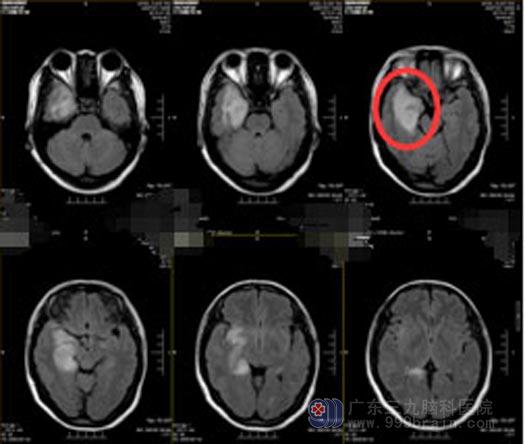

前段时间,朱女士再次出现四肢抽搐,当地医院头颅MR检查提示“右侧颞叶病变”。 入住广东三九脑科医院综合神经外科,结合患者症状、体征、头颅MR检查,诊断“右侧颞叶病变”考虑胶质瘤,且肿瘤体积较大,周围脑组织水肿明显,有手术指征,肿瘤位于颞叶,累及脑功能区,为最大程度降低脑损伤,预防术后后遗症,采用唤醒麻醉下肿瘤切除术,导航定位右侧颞岛叶肿瘤位置,见皮层下肿瘤呈胶冻状,血供一般,在显微镜下分块切除。

手术前